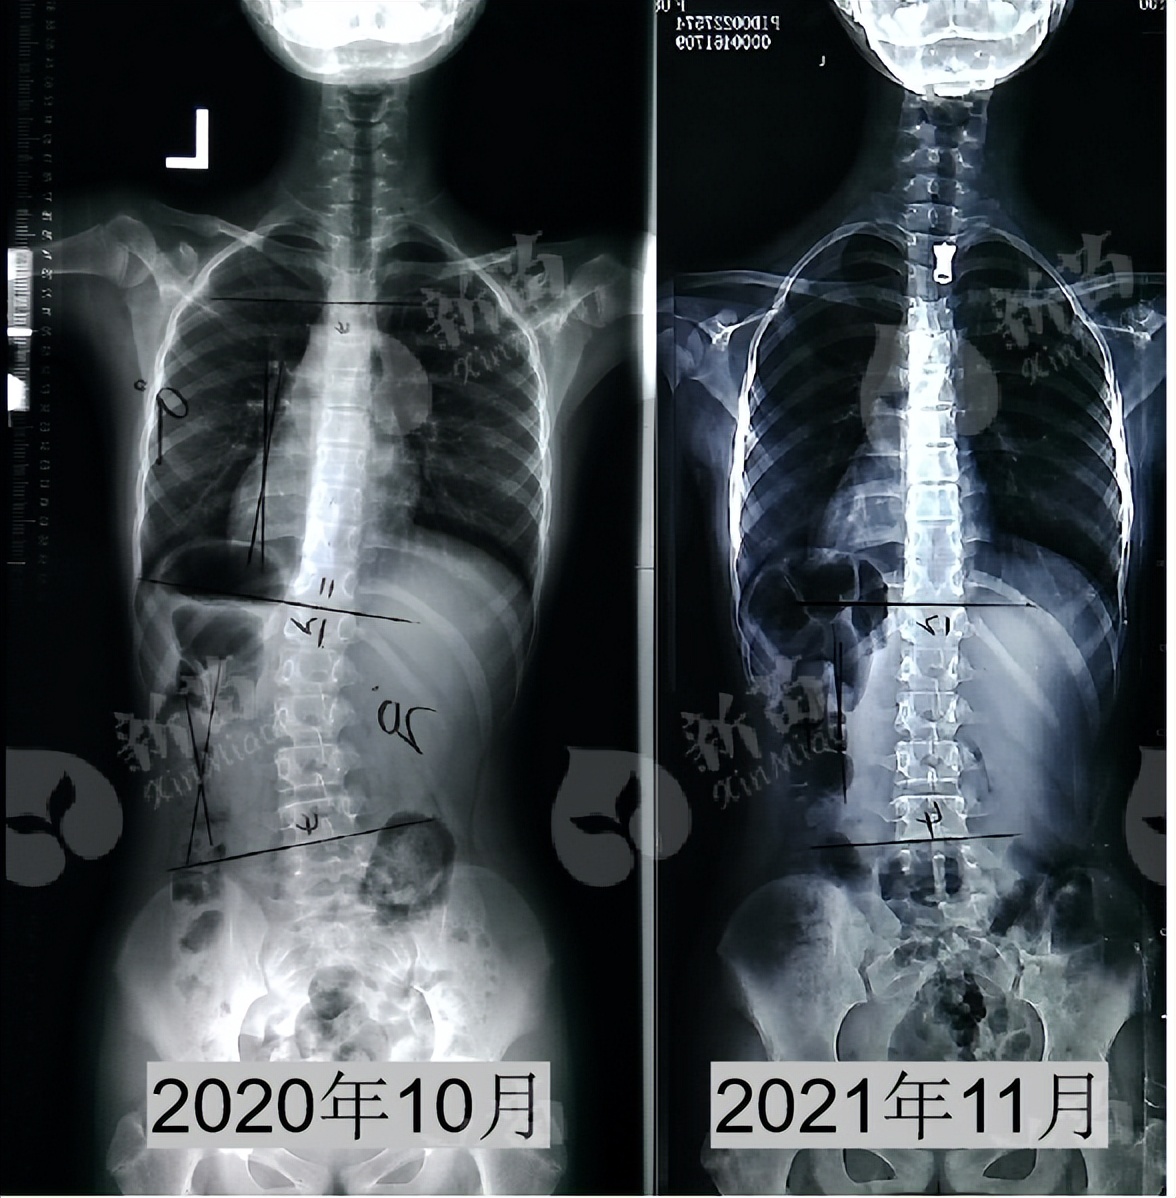

2021年11月复诊,小乔 脱下支具2天 后拍摄全脊柱X光片,脊柱侧弯角度腰弯 20°降至4° 。背部外观上,两侧肩胛骨也较以前对称,两侧腰部基本对称。

(小乔治疗前后对比)

小乔是12岁拍片发现的脊柱侧弯,这个年阶段的孩子仍处于 生长发育较快的时期 ,她的X光片显示侧弯20°伴椎体旋转,针对小乔的情况,结合病情后我们设定了针对性的医学形体训练和支具治疗方案。

脊柱侧弯度数能够改善到 10°以下 ,对小乔来说是一个非常好的治疗效果。

首先,小乔发现侧弯时是12岁,X光片显示 Risser征0级 ,正常情况下, 青少年Risser征在3级以内都是脊柱侧弯矫正的黄金期 ;加上小乔柔韧性好,通过以支具矫正与形体训练相结合的有效治疗,小乔的脊柱基本回直。

(首次佩戴支具,侧弯T4-T11右侧凸矫正至0°,T12-L4左侧凸矫正至2°)